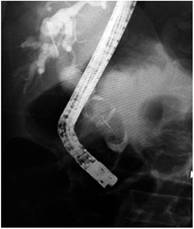

La enfermedad litiásica biliar afecta a más de 20 millones de adultos en Norteamérica, con un costo anual de 6,2 miles de millones de dólares 1. Aproximadamente el 85% al 90% de los cálculos biliares pueden extraerse con un balón o una canastilla después de realizar una esfinterotomía o una dilatación papilar con balón (DPB) 1,2. Cerca del 10% al 15% de los pacientes con coledocolitiasis presentan un cálculo gigante definido como aquel que mide más de 10 mm a 15 mm (Figura 1). La extracción de estos puede ser problemática aun para endoscopistas experimentados. Casi todos los pacientes con esta patología pueden ser tratados endoscópicamente, y la mayoría de los cálculos se extraen con la realización de una esfinterotomía (EFT), litotripsia mecánica (LM) o dilatación papilar con balón grande (DPBG) 1,3,4,5.

La DPBG después de una EFT limitada o pequeña fue descrita en 2003 por Ersoz y colaboradores para la remoción de cálculos >10 mm o múltiples cálculos biliares 1,8,9,12. Se utiliza para crear una mayor apertura del orificio biliar con un balón de diámetro grande (12 mm a 20 mm) para simplificar la remoción de cálculos gigantes y difíciles del conducto biliar y como una alternativa a la LM, ya que esta consume tiempo, puede generar impactación o fractura de la canastilla de Dormia y aumentar el riesgo de eventos adversos. La EFT es inicialmente recomendada como paso previo a la DPBG, ya que se cree que está asociada con una disminución del riesgo de pancreatitis pos-procedimiento (Figura 2) 8,9,13,14. Puede utilizarse como método inicial cuando se documentan cálculos gigantes en las imágenes o cuando la remoción convencional con EFT y canastilla han fallado 14,15,16.

Los factores de riesgo asociados con el procedimiento que pueden estar relacionados con la presencia de eventos adversos incluyen el tamaño de la EFT, el diámetro del balón utilizado y la forma de inflar el balón 8,9,14. El diámetro del conducto biliar distal es el factor más importante al seleccionar el diámetro del balón que se va a utilizar, ya que la dilatación más allá del diámetro del colédoco aumenta el riesgo de perforación y, por ende, el diámetro máximo de inflado del balón no debe exceder el diámetro mayor del colédoco distal. Aunque el diámetro de los balones para DPBG oscila de 12 mm a 20 mm, en la mayoría de los casos se utilizan balones de 12 mm a 15 mm para prevenir eventos adversos (Figura 3). El inflado rápido y forzado del balón a través de un conducto biliar distal estrecho puede llevar a perforación y sangrado. Por esto, el balón siempre debe inflarse lenta y gradualmente hasta que desaparezca su cintura (Figura 4). Si la cintura del balón no desaparece, puede sugerir la presencia de una estenosis biliar oscura (oculta), y no se debe dilatar por encima de este nivel. En ese caso, se debe desinflar el balón para evitar el riesgo de complicaciones. En los pacientes con estenosis biliares evidentes, o en conductos no dilatados, la DPBG no se recomienda debido al riesgo de perforación 17,18. La duración usual de la DPBG es de 30 a 60 segundos después de desaparecer la cintura, aunque en diferentes estudios respecto del tiempo de dilatación oscilan entre los 10 segundos y los 180 segundos 14,18; se requieren estudios adicionales para establecer la duración óptima de la dilatación. En nuestra serie, el tiempo de dilatación fue de 60 segundos.